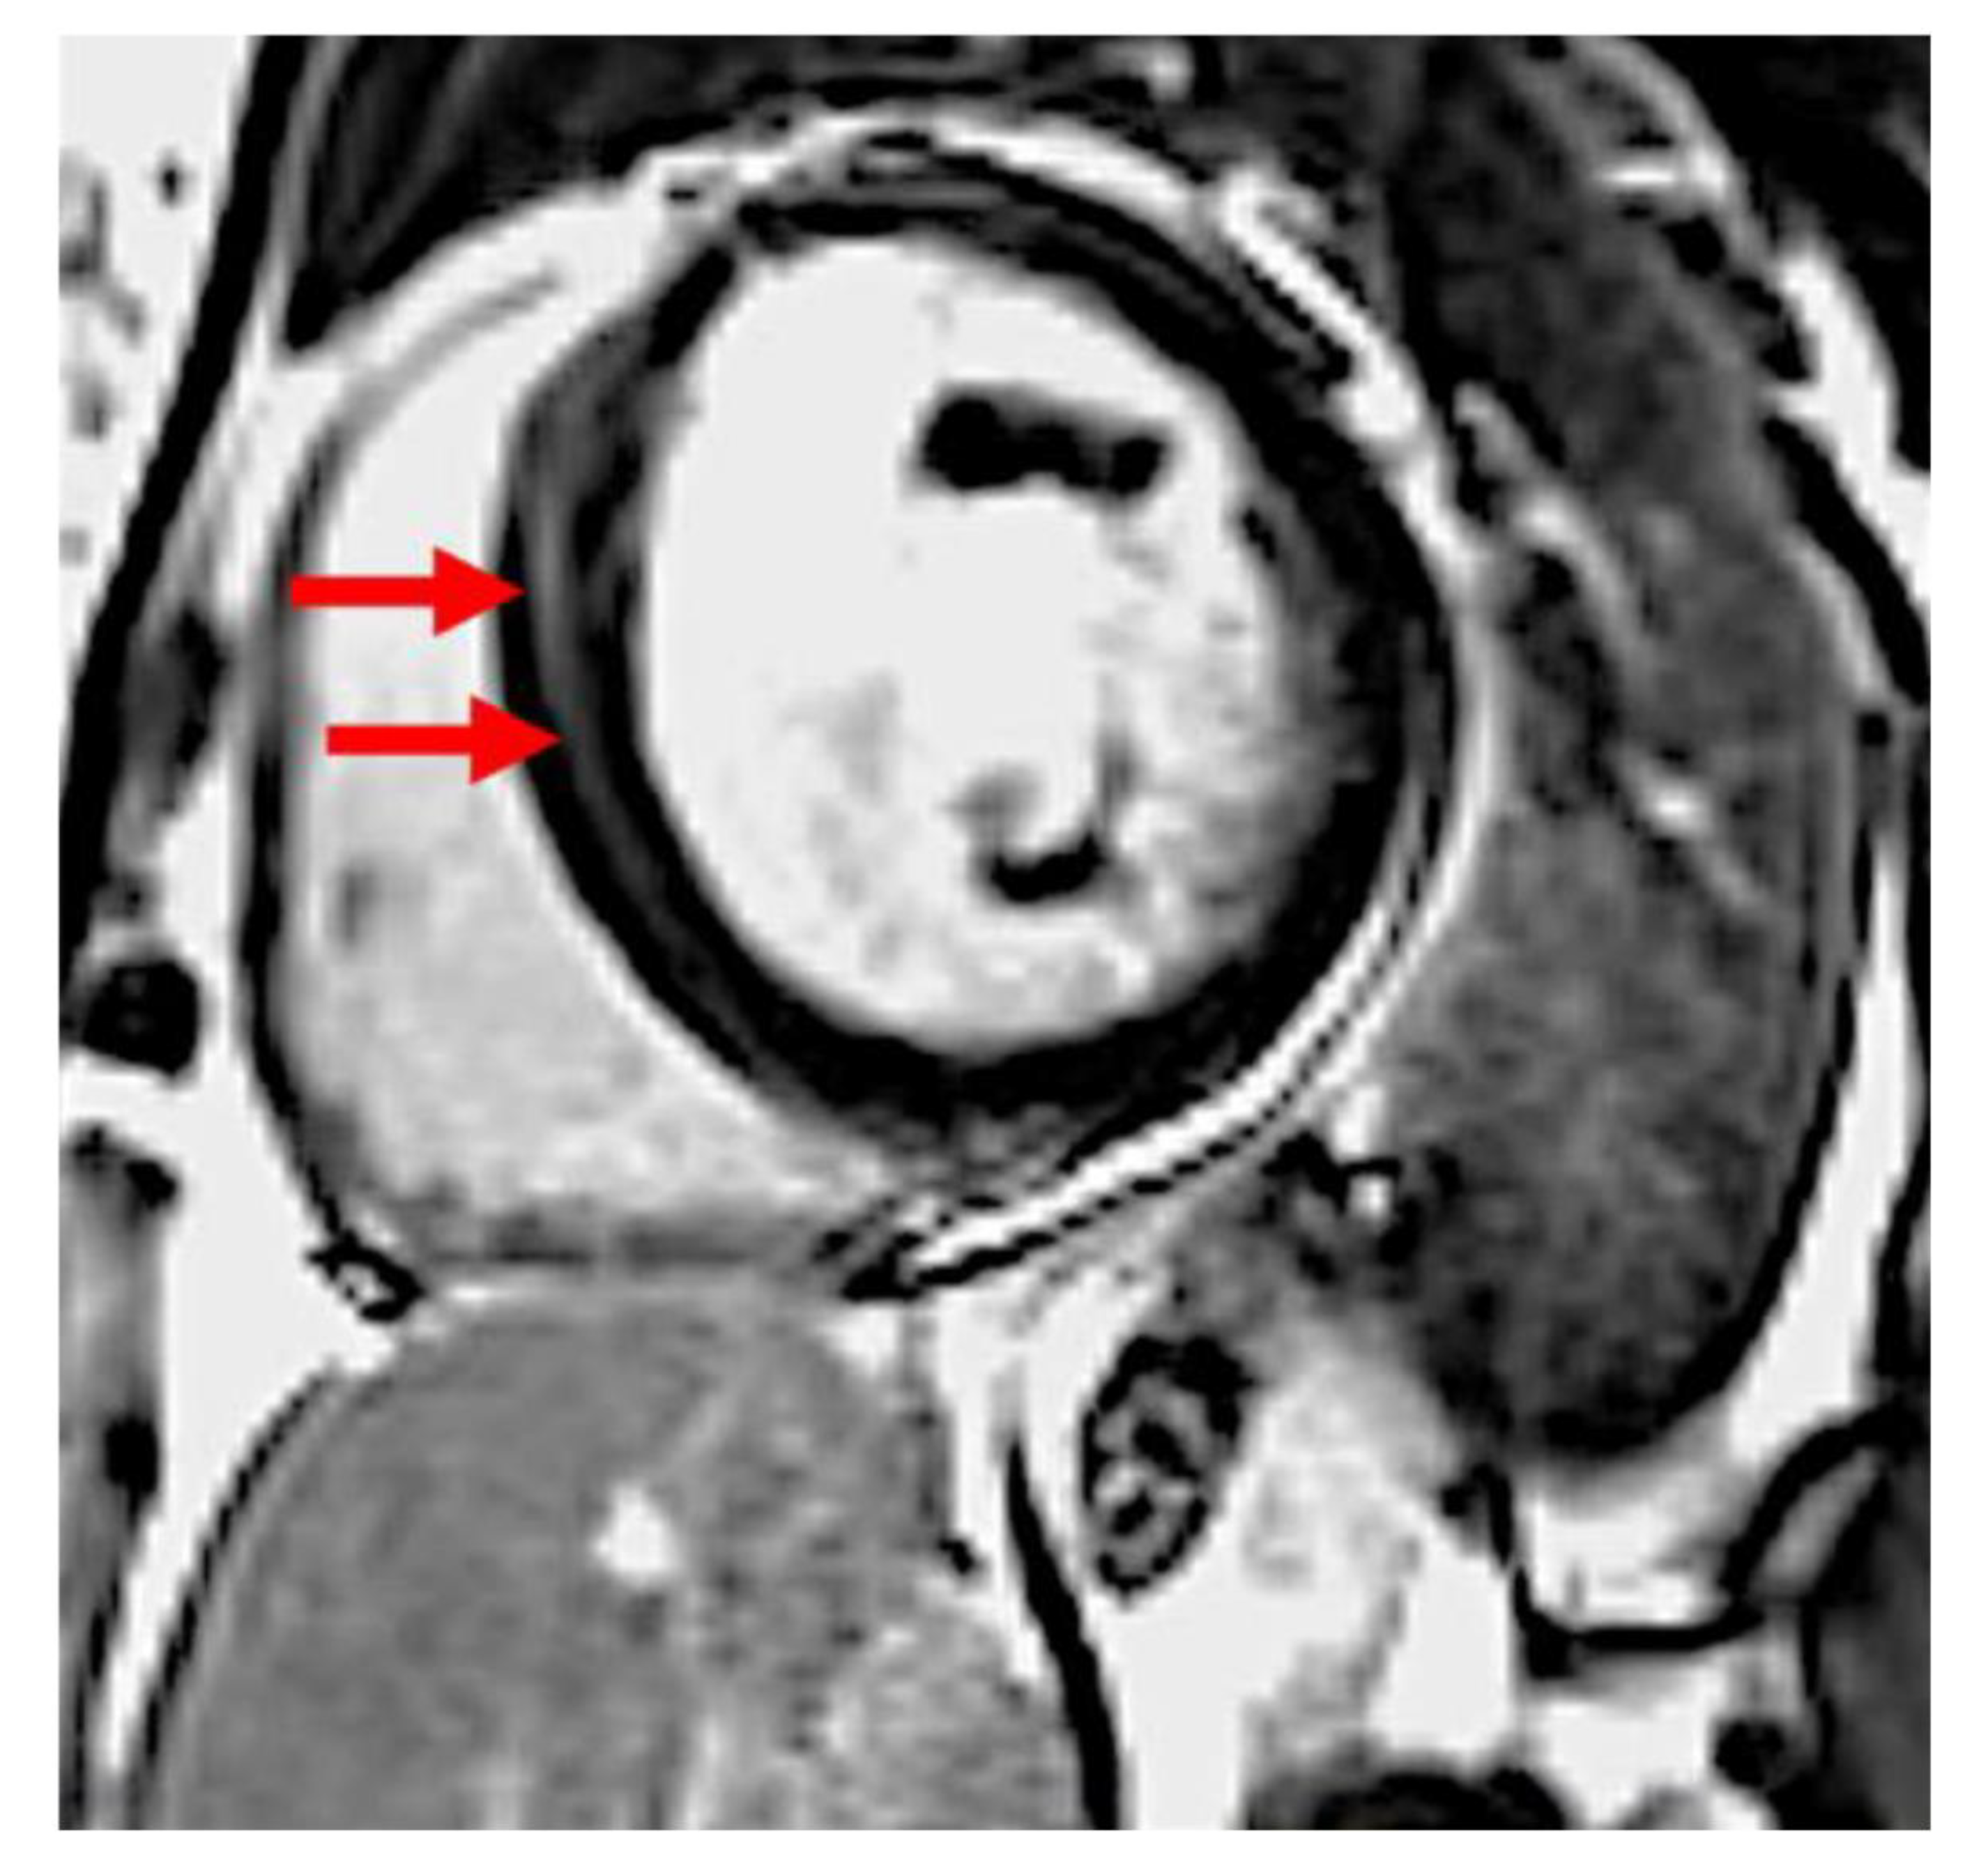

Cardiovascular magnetic resonance imaging was performed by using a 1.5-T scanner (Sonata and Avanto fit, Siemens, Erlangen, Germany). Cine images were acquired by breath-hold, electrocardiographic-gated, segmented k-space steady-state free-precession (SSFP) technique using 25 phases per cardiac cycle. LGE images were obtained in the long-axis and short-axis imaging planes by using a breath-hold segmented inversion recovery sequence implemented 10–15 min after intravenous administration of 0.1 mmol/kg of gadobutrol (Gadovist, Bayer, Berlin, Germany). The presence of left ventricular LGE was initially visually assessed by two independent experienced observers (JPM and LM). If positive, quantification was performed using the using CVi42 software (Circle Cardiovascular Imaging Inc., Calgary, AB, Canada) with a signal intensity threshold of >6 standard deviations above the remote myocardium (Figure 1) [13]. The extent of LGE was presented as a percentage of the total LV mass.

Figure 1.

Late gadolinium enhancement in basal antero-septal wall in a patient with peripartum cardiomyopathy. Arrows indicate abnormal signal in the septum.